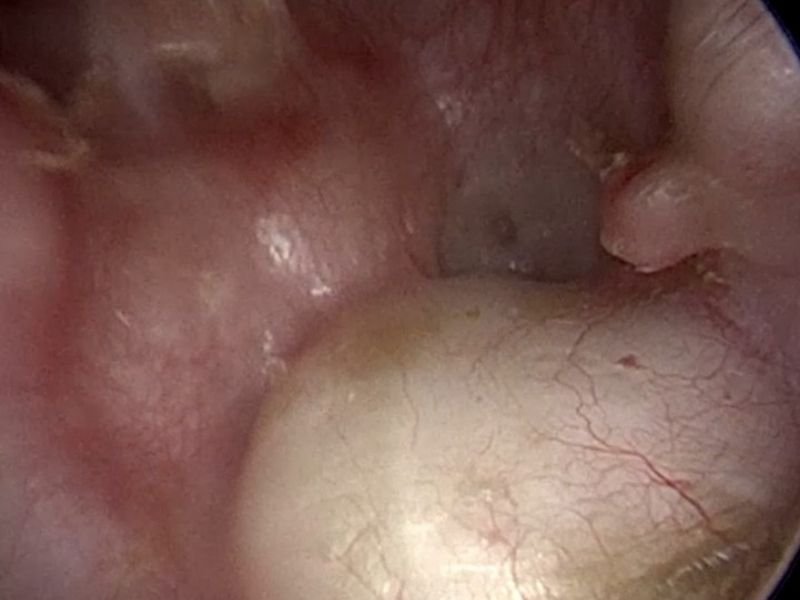

Mastoidectomia: O Procedimento Cirúrgico

A mastoidectomia é a cirurgia indicada para tratar a mastoidite crônica em casos onde os tratamentos conservadores, como antibióticos, não surtiram efeito. O procedimento visa remover as áreas afetadas do osso mastoide, possibilitando a drenagem de secreções e a eliminação da infecção.

Como é realizada a cirurgia de mastoidectomia?

A cirurgia de mastoidectomia é realizada com anestesia geral e, geralmente, leva entre duas a três horas, dependendo da complexidade do caso. Durante a cirurgia, o cirurgião realiza uma incisão atrás da orelha, que permite o acesso à região mastoide. O tecido inflamado e as áreas infectadas do osso são removidos, permitindo a drenagem de secreções e a melhoria do fluxo sanguíneo na região. Em casos mais graves, pode ser necessário remover uma porção maior do osso.